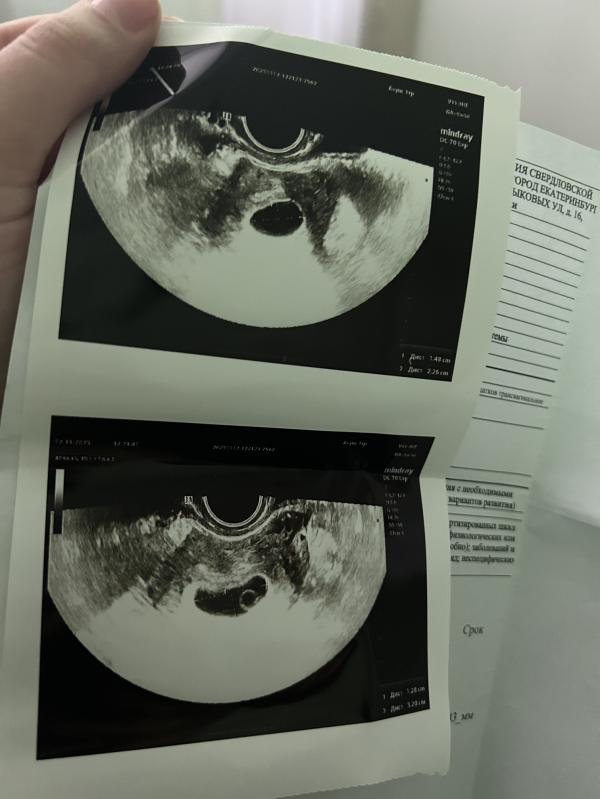

Девочки два узи, говорят что беременность анэмбриональная, срок 7-8 недель

Ходила сегодня платно на повторное узи сказали что видят два желтых мешка( большие) но эмбрионы не визуализируются, говорят шансов нет идти на чистку, что делать не знаю. Может у кого-то было такое.

(Изначально на первом узи не сказали что два мешочка)